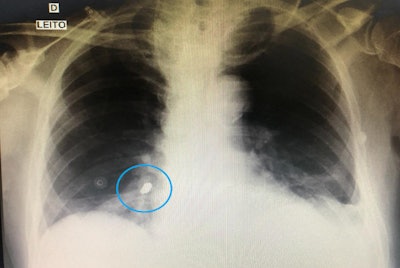

A chest x-ray revealed a foreign body, eventually identified as a dental crown, in a man's right lower lobe bronchus. All images courtesy of Hadad et al. Licensed under CC BY-NC-ND 4.0.Emergency situation

After the tube was placed, the patient underwent a chest x-ray to ensure the tube was in the proper location. However, imaging also revealed a foreign body shaped like a dental prosthetic crown in his right lower lobe bronchus.